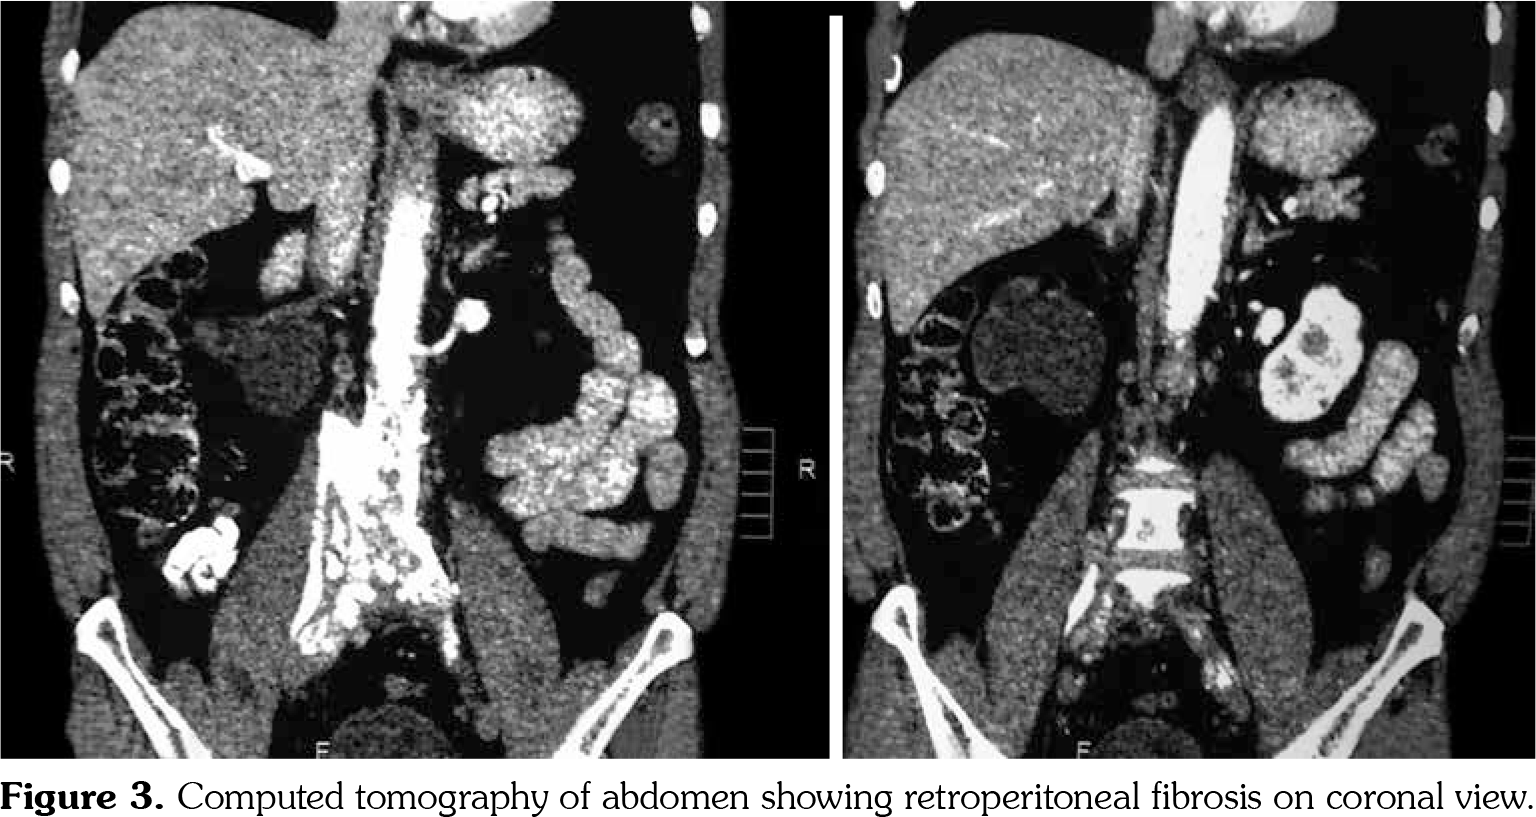

On investigations, his complete blood count was normal. Erythrocyte sedimentation rate was 88 mm in first hour. Random blood sugar was 93 mg/dL. His serum urea was 26 mg/dL and serum creatinine was 1.1 mg/dL. Liver function tests were within normal limits. Chest X-ray revealed non-homogenous opacities in bilateral lung fields. Pulmonary function tests revealed forced expiratory volume in one second (FEV1) of 61% and forced vital capacity (FVC) of 73%. FEV1/FVC ratio was 84%. Two-dimensional echocardiography was within normal limits. Ultrasonography of the abdomen revealed small-sized right kidney (6.9x2.9 cm) with dilated pelvi-calyceal system and dilated proximal ureter. Computed tomography (CT) of the abdomen revealed medial deviation of right ureter and presence of retroperitoneal soft tissue along infra-renal aorta and peri-caval area with calcification extending up to iliac vessels suggestive of RPF (Figures 1, 2, 3, and 4). High-resolution CT of the chest confirmed presence of interstitial lung disease (ILD). ANA profile (ENA) revealed that anti-U1 snRNP was strongly positive. Rest of the autoantibodies were negative. His serum immunoglobulin G levels were within normal limits. Thus, we arrived at a diagnosis of MCTD with RPF and ILD. He was started on mycophenolate 720 mg twice daily, hydroxychloroquine 200 mg once daily and deflazacort 6 mg once daily for MCTD, pirfenidone 400 mg twice daily for ILD and tamoxifen 20 mg once daily for RPF. On follow-up at six months, he was doing physically well. His symptoms of cough were reduced and dyspnea improved from NYHA class IV to class II. Repeat pulmonary function tests revealed FEV1 of 59%, FVC of 71% and FEV1/FVC ratio of 84%. However, repeat ultrasonography of the abdomen did not reveal any significant change in pelvi- calyceal system.

In 1972, Sharp et al.,[1] recorded a group of patients who had clinical features of SLE, SSc and PM with high titers of anti-extractable nuclear antigen antibody. They published it as a new disease entity: MCTD. Since then, there has been an increasing number of classification criteria published for the diagnosis of MCTD, namely, Kasukawa et al.[3] Alarcon-Segovia and Villareal[4] and Kahn and Appelboom.[5] There has been no consensus on clinical features owing to varied manifestations and frequent overlap of symptoms with other autoimmune conditions. However, high titers of antibodies against U1 snRNP have been found in most patients.[6] Our patient had symptoms of dysphagia, epistaxis and ocular sicca coupled with high titers of anti-U1 snRNP which led us to the diagnosis of MCTD. He also had pulmonary involvement in the form of ILD. One study showed 47% of cases of MCTD to have ILD.[7] The most frequent histological picture seen is non-specific interstitial pneumonia, followed by usual interstitial pneumonia and lymphocytic interstitial pneumonia.[8] RPF was first reported by Ormond[9] in 1948. It is a rare condition characterized by inflammation and fibrosis of the retroperitoneum, around the infra-renal portion of abdominal aorta and iliac arteries and usually entraps ureters and inferior vena cava.[10] A recent study reported incidence of RPF around 1.3 per 100,000 population per year in Netherlands.[11] The mean age of presentation is around 50 years with male predominance (2:1-3:1). Abdominal CT and magnetic resonance imaging are the investigations of choice for the diagnosis of RPF and they reveal a homogenous mass near the lower abdominal aorta and iliac arteries that surround and displace the ureters medially. Medical therapies for RPF include steroids, tamoxifen, other immunosuppresives such as azathioprine, mycophenolate and anti-CD20 antibody such as rituximab. In one single-center prospective observational study of 55 patients with RPF treated with tamoxifen monotherapy for a minimum of two years, 47 (85%) patients reported substantial resolution of symptoms after a median treatment duration of three weeks. There was a mass regression in 39 (71%) patients at four months and 47 (85%) patients at eight months of follow-up, respectively. Recurrence- free survival in patients with treatment success after post-treatment follow-up of 21 months was 68%.[12] To our knowledge, there is no previously published case report on presence of RPF in a patient of MCTD. This is indeed a rare occurrence.